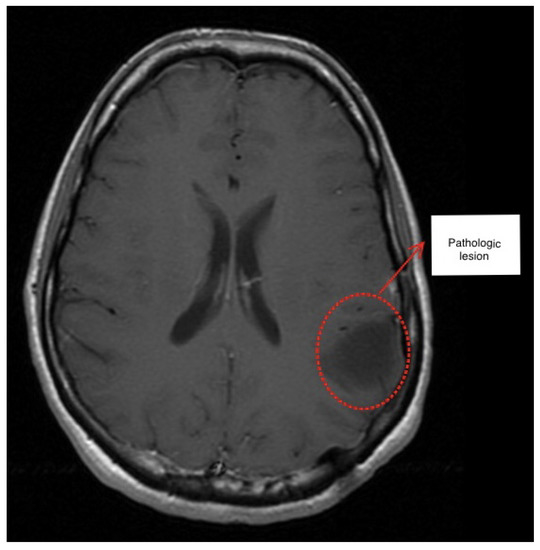

2. Description of the Methodology

3.1. First Scenario